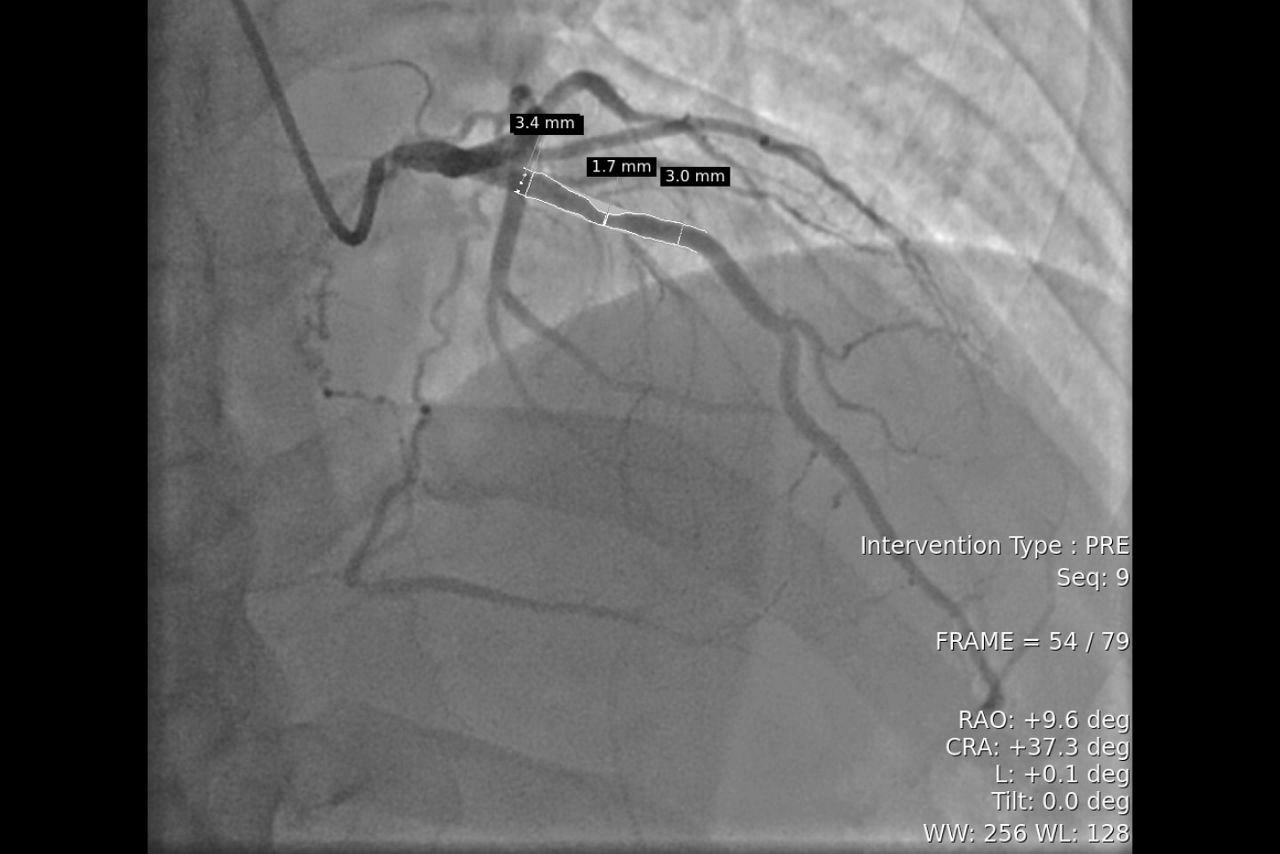

Plan

Quantitative analysis with One Touch QA

One-click access from Touch Panel. Help to plan the optimal sized stent or device by allowing for an estimation of distances and stenosis ratio.